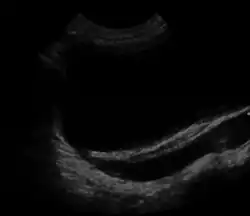

Ultrasound image showing abnormal vesicoureteral junction and dilated distal ureter resulting in primary vesicoureteral reflux (VUR). | |

Vesicoureteral reflux (VUR), also known as vesicoureteric reflux, is a condition in which urine flows retrograde, or backward, from the bladder into one or both ureters and then to the renal calyx or kidneys.[1][2] Urine normally travels in one direction (forward, or anterograde) from the kidneys to the bladder via the ureters, with a one-way valve at the vesicoureteral (ureteral-bladder) junction preventing backflow. The valve is formed by oblique tunneling of the distal ureter through the wall of the bladder, creating a short length of ureter (1–2 cm) that can be compressed as the bladder fills. Reflux occurs if the ureter enters the bladder without sufficient tunneling, i.e., too "end-on".

Insufficient submucosal length of the ureter relative to its diameter causes inadequacy of the valvular mechanism. This is precipitated by a congenital defect or lack of longitudinal muscle of the portion of the ureter within the bladder resulting in an ureterovesicular junction (UVJ) abnormality.